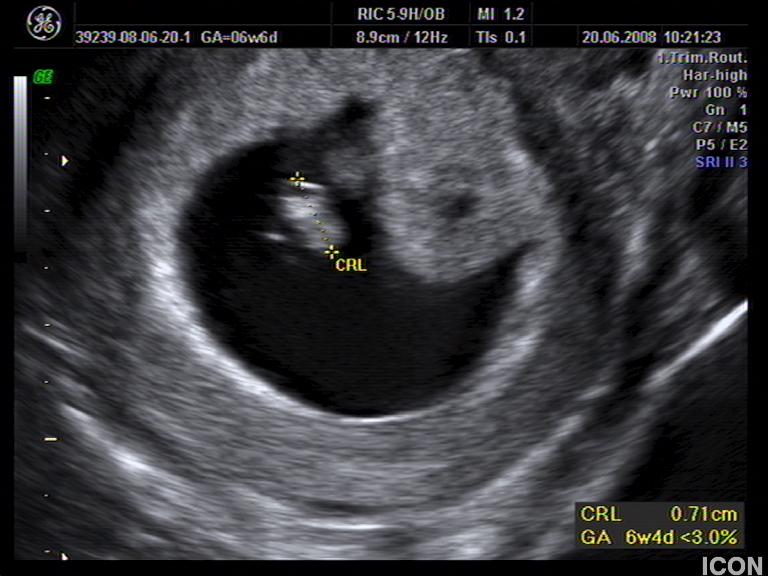

Αυχενική διαφάνεια

Η αυχενική διαφάνεια (ΑΔ) είναι η συλλογή υγρού στον τράχηλο του εμβρύου και συγκεκριμένα ανάμεσα στο δέρμα και στους ιστούς που καλύπτουν τη σπονδυλική στήλη.